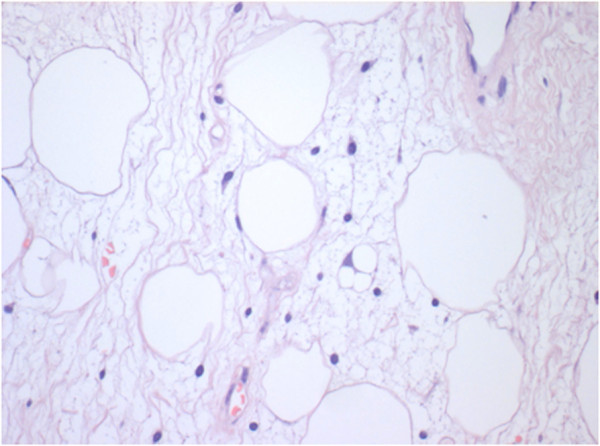

Histologic findings showed the presence of liposarcoma of mixed type (myxoid liposarcoma with areas of well-differentiated ‘lipoma-like’ liposarcoma) according to World Health Organization (WHO) recommendations (Figures 3 and 4).

Figure 3.

Scattered among mature adipocytes, atypical spindled cells and a lipoblast are shown. Note the variation in the size of the fat cells, a common feature in atypical lipomatous tumors (hematoxylin and eosin ×100).